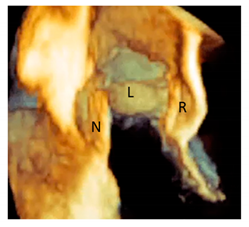

| Cusps, leaflets | The term “cusps” refers to the moving parts of the aortic root. When seen in closed position from the ventricular perspective, this component is similar to the surface of a molar tooth (called cusp). The term is used to describe the structure of the valve (i.e., unicuspidal, bicuspid, and tri-cuspid). Literally the term indicates a pointed end where two curves meet. In the aortic root, it indicates an intact interleaflet triangle with its apex reaching the sinutubular junction. The term leaflet means “small leaf”, which describes a thin, pliable layer. This term perfectly fits the leaflet aspect. N = non-coronary, L = left coronary, R = right coronary leaflets/cusps. | ![]() |